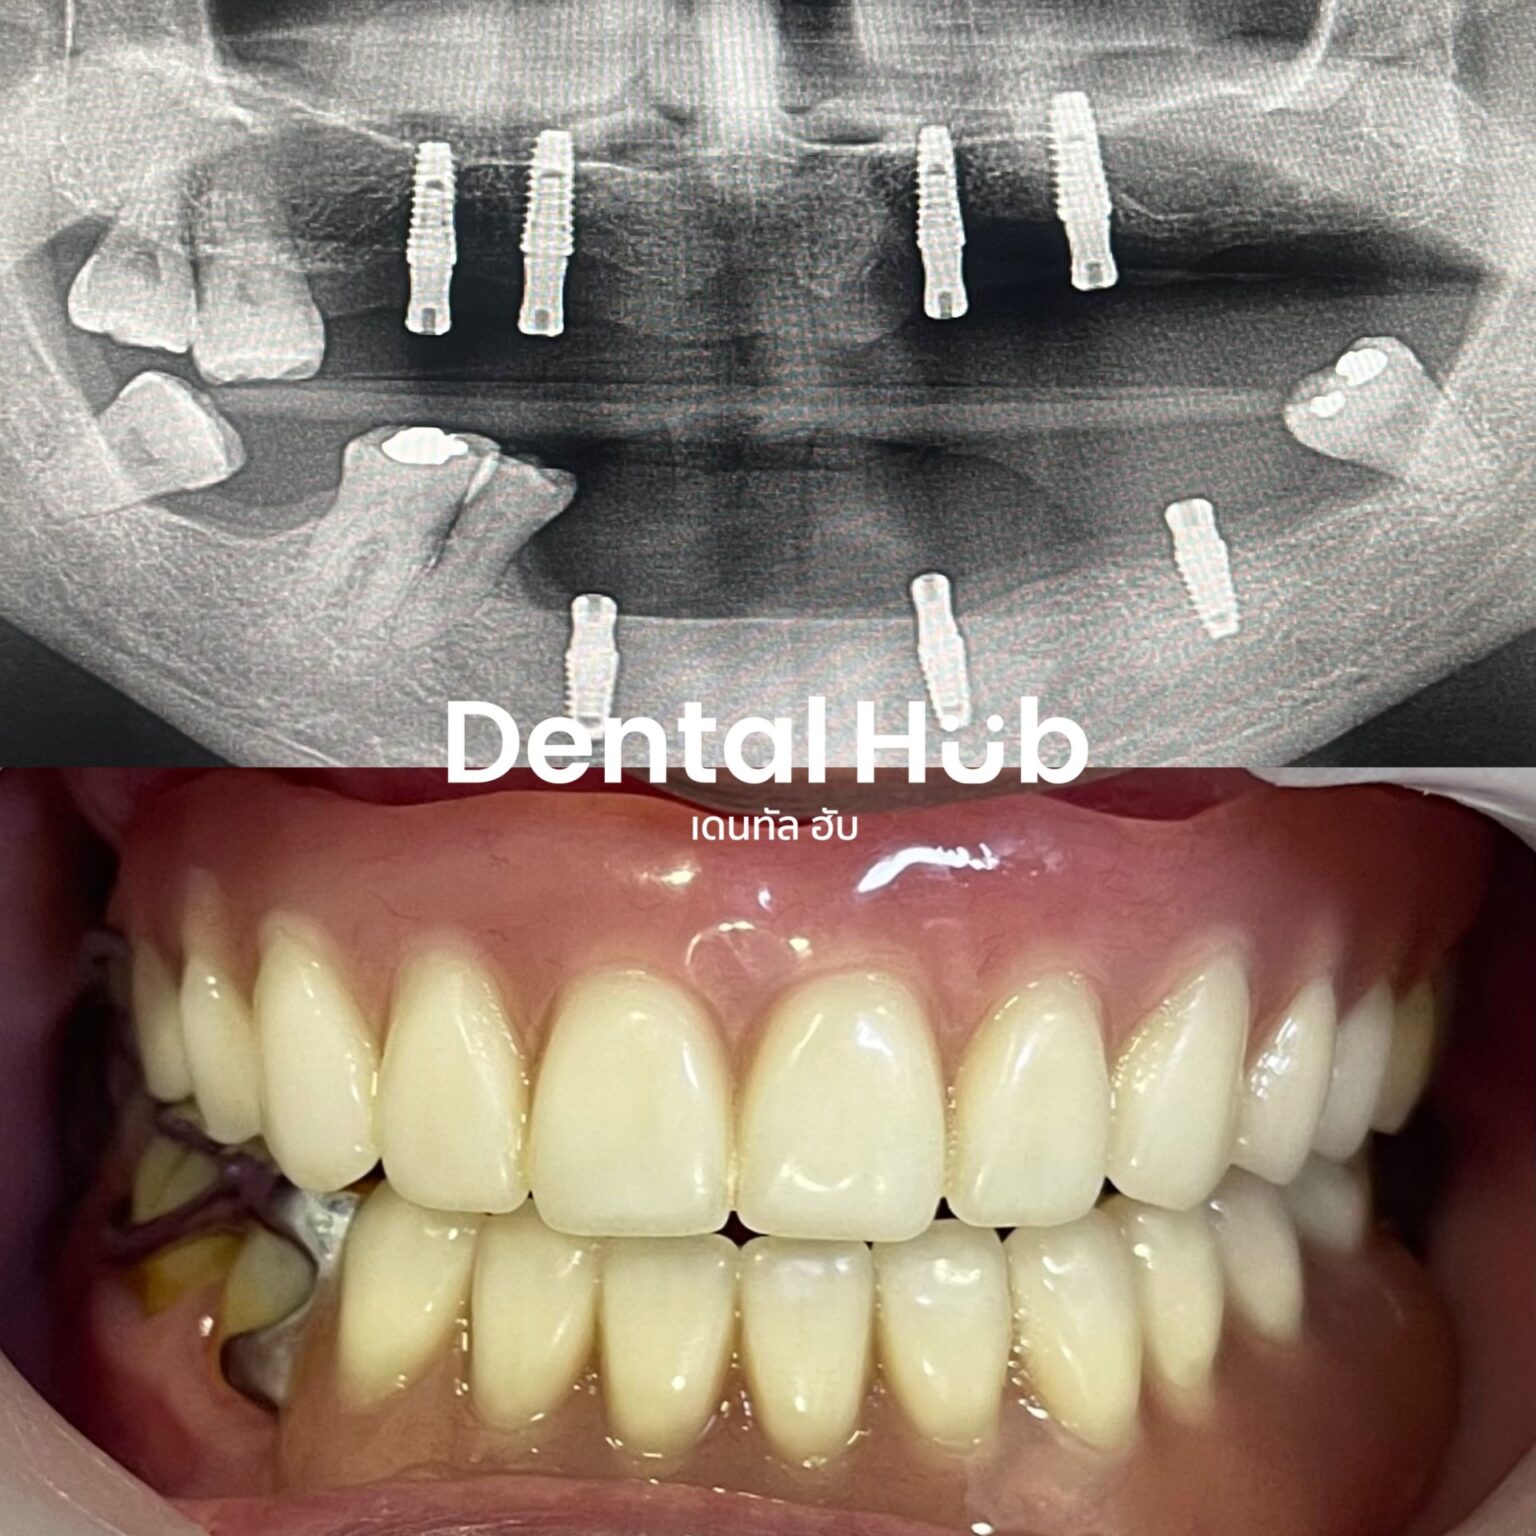

“ หมดกังวลเรื่องฟันหลอ เคี้ยวอาหารไม่ถนัด

แก้ปัญหาได้ด้วยรากฟันเทียม ”

ขั้นตอนการทำ

รากฟันเทียม ที่ เดนทัล ฮับ

ตรวจและวางแผน

ทันตแพทย์ตรวจช่องปากและเอ็กซเรย์เพื่อวางแผน การฝังรากฟันเทียมให้เหมาะสม

ฝังรากฟันเทียม

ผ่าตัดเล็กเพื่อฝังรากเทียมไทเทเนียมในกระดูก ขากรรไกร ให้รากยึดติดได้ดี

พิมพ์ครอบฟัน

หลังจากกระดูกยึดติดกับรากเทียม ใช้เวลาประมาณ 3-6 เดือน พิมพ์เพื่อทำครอบฟัน

ติดตั้งครอบฟัน

ห่างจากครั้งที่สอง 2 สัปดาห์ ทันตแพทย์ติดครอบฟัน บนรากเทียม ปรับให้เหมือนฟันธรรมชาติและใช้งานได้ดี

ฟันหลุดหายทั้งปาก

รักษาแบบไหนได้บ้าง

All-on-4

ใส่ฟันทั้งปากแบบติดแน่นถาวรพยุงด้วยรากเทียม 4 ตัว

Overdenture

ฟันเทียมแบบติดแน่นแต่ยังสามารถถอดออกได้